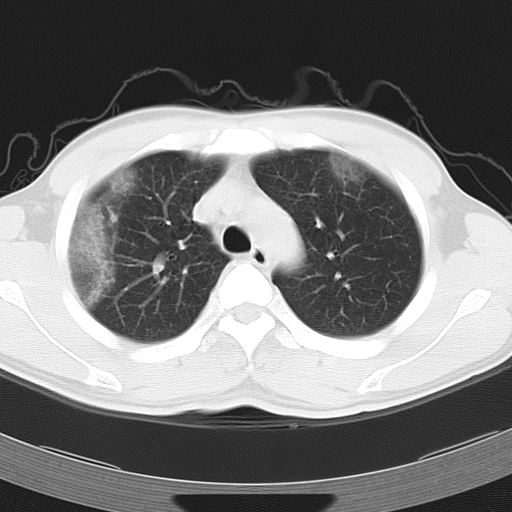

标题: CT12379:男,34岁,肺部病变,请求会诊!

男,34岁,咳嗽2~3个月,无咳血,病初有发热。

ct表现 (1)中央型:表现为蝶翼状浸润性阴影对称分布于两侧肺门周围,其内可见支气管充气征,病变区与正常肺组织分界清楚。(2)外围型:表现为多发性条片状、斑片状及斑块状高密度影,弥散、对称或不对称分布于两肺或一侧肺外围部位。病变区与正常肺组织及脏层胸膜面分界清晰,呈地图样改变。hrct可显示小叶间隔增厚及肺小叶内淡淡的密度增高影等细微结构,同时易发现肺大疱、肺气囊及节段性肺不张。

再仔细阅读该病人的ct片,我们不难发现,病例所表现的正是外围型的肺泡蛋白沉积症表现,即:为多发性条片状、斑片状及斑块状高密度影,弥散、对称或不对称分布于两肺或一侧肺外围部位。病变区与正常肺组织及脏层胸膜面分界清晰,呈地图样改变。

所以,我本人的意见也是趋向于肺泡蛋白沉积症的诊断,尽管最后诊断还是要根据支气管肺泡灌洗物检查或经纤支镜或剖胸活检作出病理诊断。或痰液检验:咳出的痰经80%乙醇固定,pas染色有15%阳性的脂质。